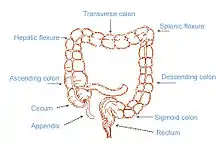

| The image shows the 4 parts of the colon (ascending, transverse, descending and sigmoid) and the rectum. Faeces are transported along and stored in the rectum before excretion | |

The gastrointestinal tract has a complex control that relies on coordinated interaction between muscular contractions and neuronal impulses.[3] Faecal incontinence or constipation occurs when there is a problem with the normal bowel functioning; this could be for a variety of reasons. The normal defecation pathway involves contractions of the colon in order to help mix the contents, absorb water and propel the contents along the intestine. This results in the faeces moving from the colon to the rectum.[4] The presence of stool in the rectum causes a reflexive relaxation of the internal anal sphincter, so the contents of the rectum can move in to the anal canal. This causes the conscious feeling of the need to defecate. At a suitable time our brain can send signals causing the external anal sphincter and puborectalis muscles to relax as these are under voluntary control and this allows defecation to take place.[4][5]